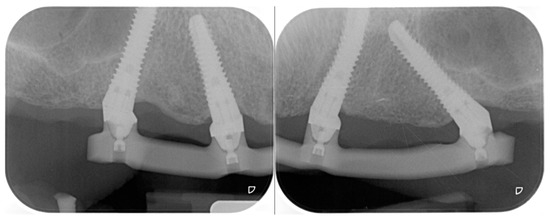

2.2. Second Step: From FDP to Implant-Supported Overdenture